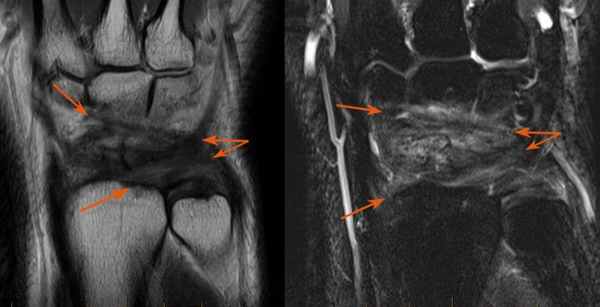

Результат МРТ правого лучезапястного сустава (рис. 2), подтвердил клиническое предположение о повреждении ладьевидно-полулунной связки, который заключался в нарушении целостности структуры связки. Также были выявлены признаки асептического некроза ладьевидной кости в стадии отека костной ткани.

Рис. 2. МРТ-исследование правого лучезапястного сустава. Получены протон взвешенные изображения с подавлением сигнала от жировой ткани (PD FAT SAT) в аксиальной, сагиттальной и фронтальной плоскостях, Т1 взвешенные изображения во фронтальной плоскости. На полученных сканах определяется: 1 – увеличение ладьевидно-полулунного сустава вдвое по сравнению с соседними; 2 – вдоль оси ладьевидной кости отмечается скопление жидкости, что можно расценить, как продольный перелом ладьевидной кости, либо отек костной ткани

После операции лучезапястный сустав фиксировался иммобилизационной повязкой сроком на 4 недели. По окончанию срока иммобилизации пациентке была рекомендована постепенная разработка лучезапястного сустава, исключающая осевые нагрузки. Через 6 недель с момента операции пациентке было выполнено МРТ исследование для осуществления контроля положения восстановленной связки (рис. 5).

Рис. 5. МРТ исследование правого лучезапястного сустава. На МРТ сканах во фронтальной плоскости: 1) отмечается восстановление пространства между ладьевидной и полулунной костями, отчетливо видна связка; верифицируется биодеградируемый пин и якорный фиксатор в ладьевидной кости; 2) отмечается синовит лучезапястного сустава и отсутствие отека костной ткани ладьевидной кости